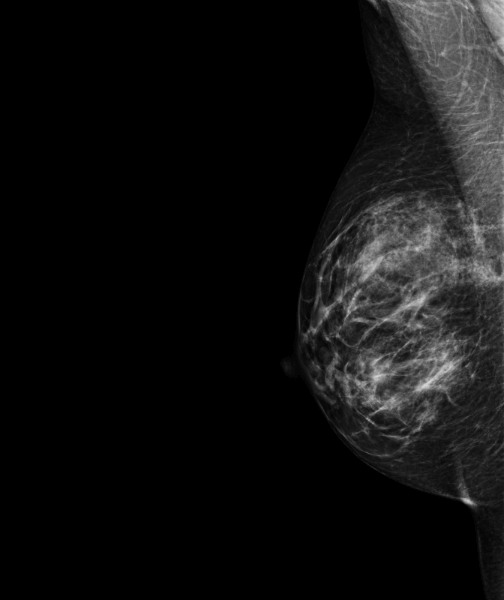

Le radiologue retrouve en échographie une masse ovale de 30 mm.L’IRM réalisée confirme l’absence de prise de contraste suspecte. Cette masse trouvée en échographie n’est donc pas maligne.

Il s’agissait donc d’un vrai négatif et non d’un faux négatif comme l’avait supposé le radiologue.